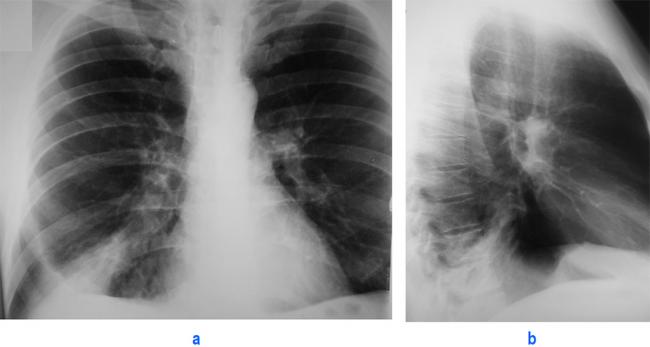

Помимо опроса и объективного осмотра, включающего перкуссию и аускультацию грудной клетки, проводят рентгенологическое исследование в двух положениях тела (в 2-х проекциях). Это основной метод обнаружения ателектазов легких.

На рентгеновских снимках выявляют следующие признаки, указывающие на спадение легочной ткани:

Однородное затемнение в области поражения. Размеры тени зависят от вида ателектаза: при долевом выявляется обширное затемнение, при сегментарном — в виде клина или треугольника, расположенного вершиной к корню легкого, дольковые ателектазы множественные и похожи на очаговую пневмонию. Дистензионный ателектаз расположен низко, около диафрагмы, имеет небольшие размеры и вид поперечных полос или темных дисков. Смещение органов: при компрессионном ателектазе смещение наблюдается в здоровую сторону, так как на стороне поражения давление больше, при обтурационном, наоборот – смещение будет в сторону ателектаза, так как на стороне поражения нарастает притягивающее отрицательное давление. Подъем купола диафрагмы – это видно по расположению печени.

Помимо всего перечисленного выше, рентгеноскопия, то есть исследование «вживую», позволяет увидеть куда смещаются органы в зависимости от фазы дыхания, кашля. Это является дополнительным признаком ателектаза, помогающим выявить тип болезни.

Если диагноз непонятен, рентгенологическое обследование дополняют компьютерной томографией. При перекрытии просвета бронхов выполняют бронхоскопию – осмотр по ходу бронхов с помощью зонда с камерой, который вводят в дыхательные пути.

При исследовании обнаруживают причину блока и уровень его расположения.

Длительные ателектазы требуют проведения контрастных методов исследования: бронхографии и ангиопульмонографии. Исследование дает информацию о глубине поражения левого и правого легкого, выявляет деформацию бронхов, а также оценивает ход сосудов.